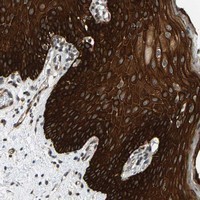

- Experimental details

- Immunohistochemical staining of human oral mucosa with SFRP5 polyclonal antibody (Cat # PAB21248) shows strong cytoplasmic positivity in squamous epithelial cells at 1:50-1:200 dilution.

- Validation comment

- Immunohistochemistry (Formalin/PFA-fixed paraffin-embedded sections)